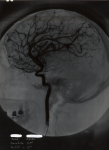

7029 Stéréoscope radiographique - radiographie de profil d'une carotide gauche

7031 Stéréoscope radiographique - radiographie profil carotide gauche à 5 degrés